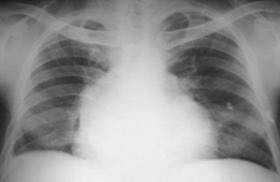

2-1 普大型心,左右心房,心室均扩大,肺动脉段平直

心脏x线表现

可以从胸片上来诊断,比如在胸片上可以看到类似球形心的改变.